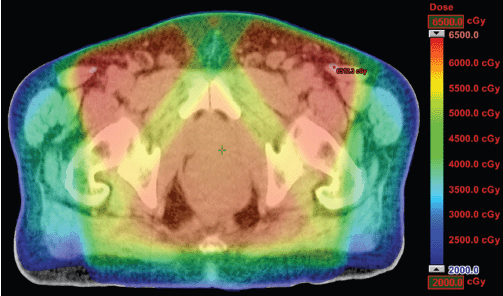

The IMRT achieved better dosimetric results in all organs tested in both the male and female patients. Compared with conformal radiotherapy, IMRT dose was reduced by 59% in the bladder, 14% in the intestine, 41% in the genitals, 26% in the iliac wings, 75% in the femoral heads and 14% in healthy tissue. The integral doses for all organs were lower with RapidArc® than with the sliding window IMRT or the conformal radiotherapy (Table 3, Figures 1–5).

Figure 3. Dosimetric results obtained with conformal radiotherapy.